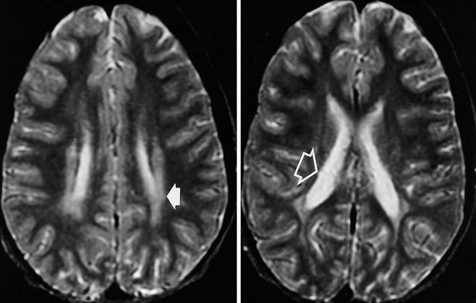

PVL is often diagnosed shortly after birth by taking an ultrasound of the baby’s head. An ultrasound is a device that uses high frequency sound waves (instead of radiation) to make an image. On the ultrasound, PVL injuries may look like swiss cheese, with dead brain tissue resembling holes on the scan. MRIs (which are more accurate) and CT scans can also be used to diagnose PVL. The damage may not be observable right away—in some cases, the injury to the brain won’t manifest fully until about eight weeks after birth. These scans are not routinely performed, but will be only be used when the doctors believe there is cause for concern—usually a premature baby, problems sucking, or unusual stiffness.